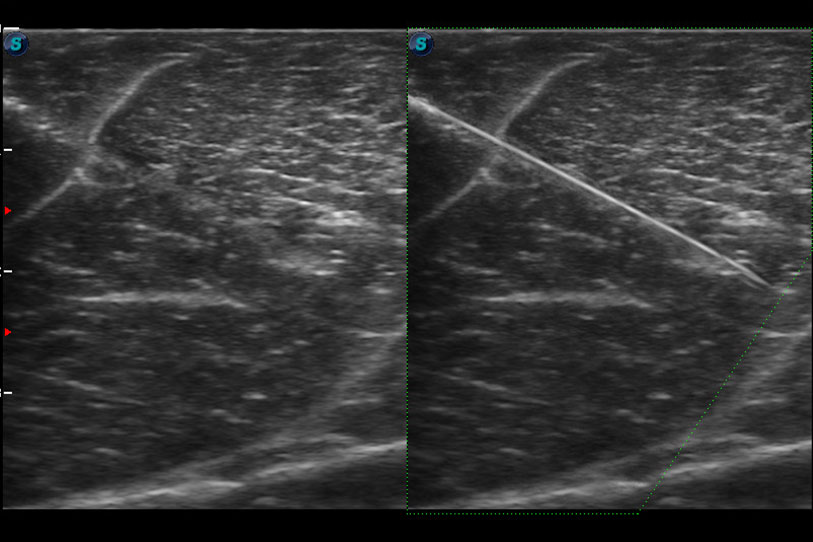

增強(qiáng)穿刺針在動物解剖結(jié)構(gòu)中的位置,提高穿刺介入的安全性和準(zhǔn)確性。